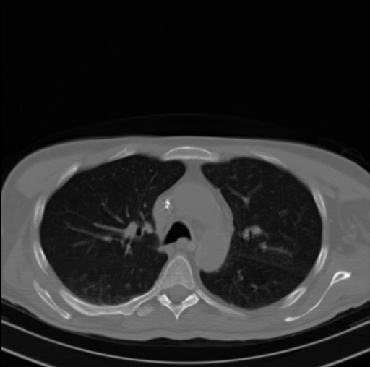

Early and reliable COVID-19 diagnosis based on chest 3-D CT scans can assist medical specialists in vital circumstances. Deep learning methodologies constitute a main approach for chest CT scan analysis and disease prediction. However, large annotated databases are necessary for developing deep learning models that are able to provide COVID-19 diagnosis across various medical environments in different countries. Due to privacy issues, publicly available COVID-19 CT datasets are highly difficult to obtain, which hinders the research and development of AI-enabled diagnosis methods of COVID-19 based on CT scans. In this paper we present the COV19-CT-DB database which is annotated for COVID-19, consisting of about 5,000 3-D CT scans, We have split the database in training, validation and test datasets. The former two datasets can be used for training and validation of machine learning models, while the latter will be used for evaluation of the developed models. We also present a deep learning approach, based on a CNN-RNN network and report its performance on the COVID19-CT-DB database.